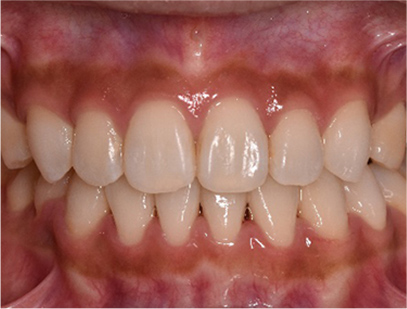

治療後

• 正面

治療前の写真と比べると上下の前歯は後方に下がりました。

そのために、鼻の下の膨らみもすっきりして、下唇も薄くなることができました。

治療期間は2年と6か月を必要としました。